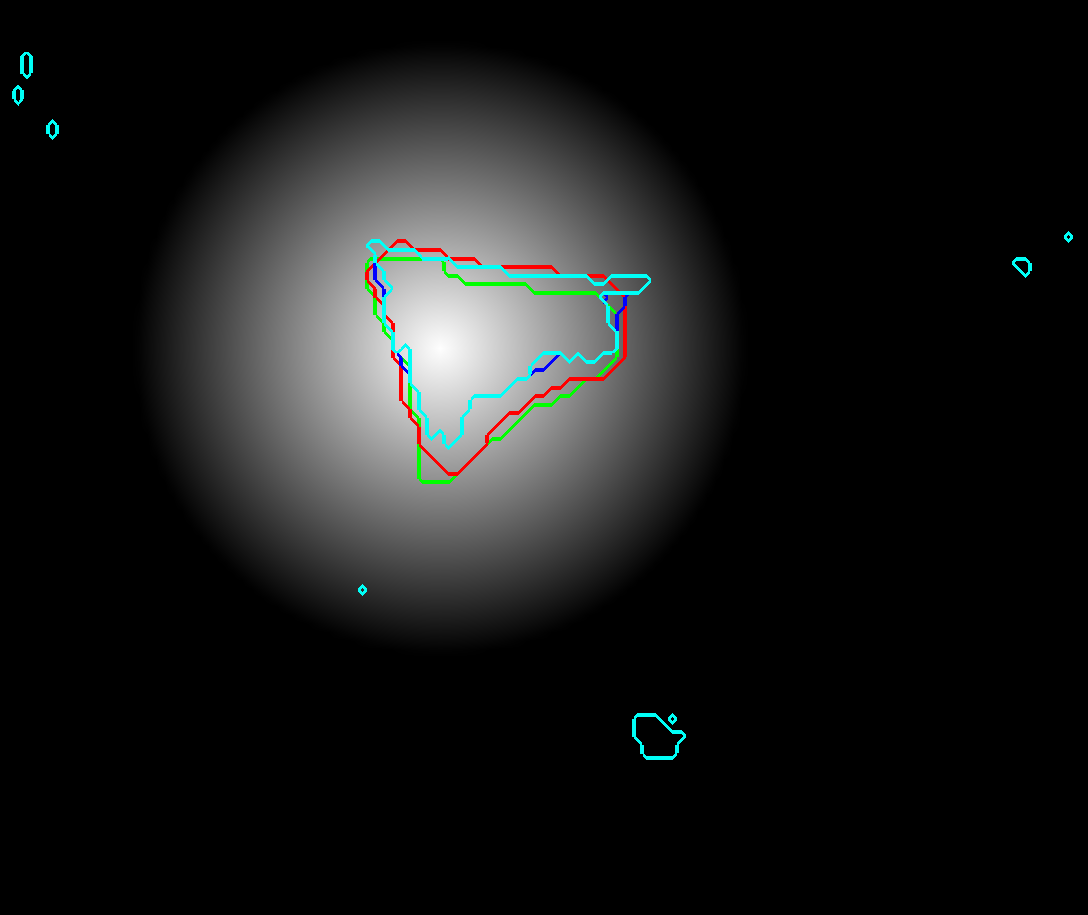

Refer to caption a) CT Refer to caption b) CNN prior Refer to caption c) Intensity based prior Refer to caption d) ACM distance map

Refer to caption e) CT Refer to caption f) CNN prior Refer to caption g) Intensity based prior Refer to caption h) ACM distance map

Refer to caption i) CT Refer to caption j) CNN prior Refer to caption k) Intensity based prior Refer to caption l) ACM distance map

Figure 2: RW input images with reference contour (green), RW contour (red), CNN with 50 % threshold (cyan) and CNN with 50 % threshold and morphological closing (blue): first column depicts CT slices; second and third column show the probabilities generated by the CNN and the intensity prior model, respectively; the distance maps generated with the ACM are shown in the fourth colulmn. Figures a - d) show public case 27, e - f) depict public case 01 and i - l) show clinical case 20.